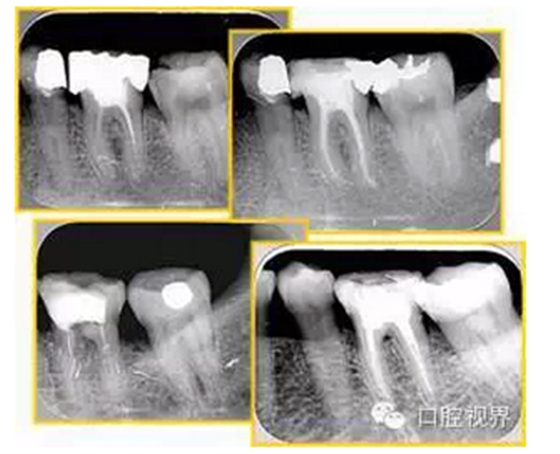

( 4 )不良根充。

不良填充與操作有關(guān),采用輔助放大設(shè)備可有效預(yù)防不良填充.解決方法:

1 )提倡使用 G-G bur 或旋轉(zhuǎn)鎳鈦銼系統(tǒng)等機用方法去除根管內(nèi)充填物。

2 )也可以使用過氯仿溶液溶解牙膠后常規(guī)根管預(yù)備。

3 )若根管內(nèi)的充填物為水門汀,須借助超聲振蕩的方法去除根管內(nèi)的不良充填物。

常見有修復性鈣化和增齡性鈣化。下面為根管鈣化 X 線片。

解決方法: ( 1 )清楚根管系統(tǒng)解剖形態(tài)。 ( 2 )安全頭的金剛砂鉆開髓,低速球鉆磨除鈣化牙本( ET20 ,ET40 ,DG-16 )。 ( 3 )徹底去除髓腔周壁的牙本質(zhì)齡。 ( 4 )借助化學性藥劑,如EDTA 等。

( 5 )初銼選用 8# 或 10#K 銼,平衡力法探察到工作長度 , H銼上下提拉法使根管擴大,提高工作效率